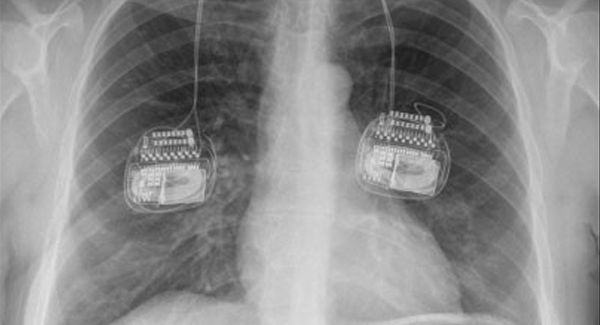

New MRI e-learning safety training: identifying medically implanted devices using plain film radiographs

An innovative new e-learning programme is designed to raise awareness of different medical implants for radiographers